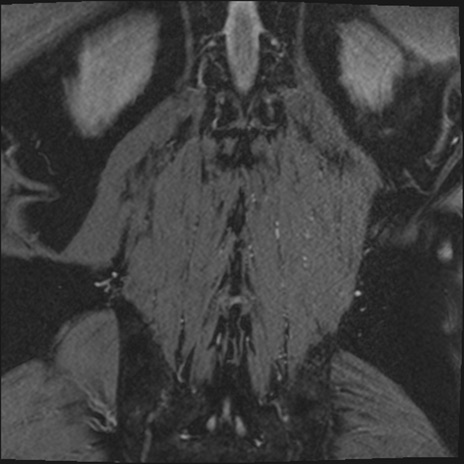

【整形】TIPS症例2 腰椎MRI 3D(冠状断像)

【症例】70歳代男性

【主訴】左下肢痛

【現病歴】2週間前くらいから腰痛、左下肢痛あり。左臀部から大腿、下腿外側のしびれが常時ある。歩行とともに同部位の痛みあり。

【身体所見】Lasegue70-/60+、Bragard-/±、PTR ±/±、ATR -/-、IP 5/5、TA 5/4、TS 5/5、EHL 右第1足趾なし/3、FHL 5/5、hypersthesia(-)、足背動脈触知良好

異常所見と診断は?